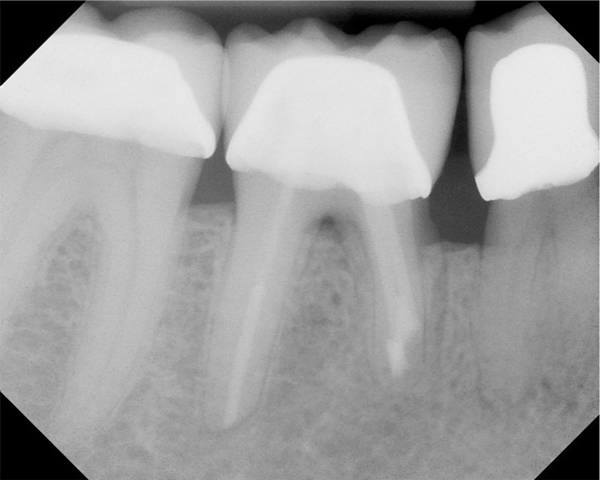

Fig 11. Preoperative radiograph. Courtesy of Dr. Guillaume Jouanny.

Fig 12. Postoperative radiography after full pulpotomy was performed. Courtesy of Dr. Guillaume Jouanny.

Fig 13. Tooth was asymptomatic at 1-year follow-up. Courtesy of Dr. Guillaume Jouanny.

Fig 14. Contralateral tooth at 1-year follow-up. Courtesy of Dr. Guillaume Jouanny.

In this case, the tooth tested vital but showed clinical signs of irreversible pulpitis. Treatment with a full pulpotomy was chosen to improve the chances the remaining pulp would survive and remain healthy. The preoperative radiograph in Figure 11 shows extensive caries in the tooth and a slightly widened apical periodontal ligament. A full pulpotomy was performed using the BC putty (Figure 12). After the putty set, a coronal restoration was placed, and an immediate postoperative radiograph was taken and viewed. At the 1-year follow-up, the tooth was asymptomatic, and the radiograph showed continued root development (Figure 13), a healthy apical periodontium, and, importantly, no calcifications in the remaining pulp (as is often seen with a calcium hydroxide therapy). A radiograph taken of the contra-lateral tooth showed similar root development (Figure 14).